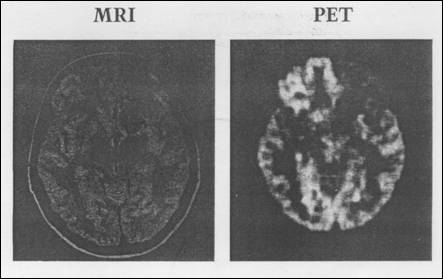

Posibilitatea investigatiilor imagistice cu ajutorul emisiei de fotoni de `nalt energie produsi prin anihilarea pozitronilor emisi de anumiti izotopi a fost demonstrat de aproape 50 de ani. Dezvoltarea tehnologiei detectorilor, precum si a algoritmilor de reconstructie de imagini, au determinat ca la sfarsitul anilor '80 PET s devin un instrument puternic `n diagnosticul medical si pentru studiul dinamic al metabolismului. Sensibilitatea mult mai mare (de milioane de ori) ca `n cazul RMN (Figura 8.21) a fcut ca PET s fie de ne`nlocuit `n studiul neuroreceptorilor din creier si al altor tesuturi, mai ales pentru concentratii nanomolare.

Figura 8.21 Malformatie arteriovenoas. PET indic metabolism deficitar al glucozei